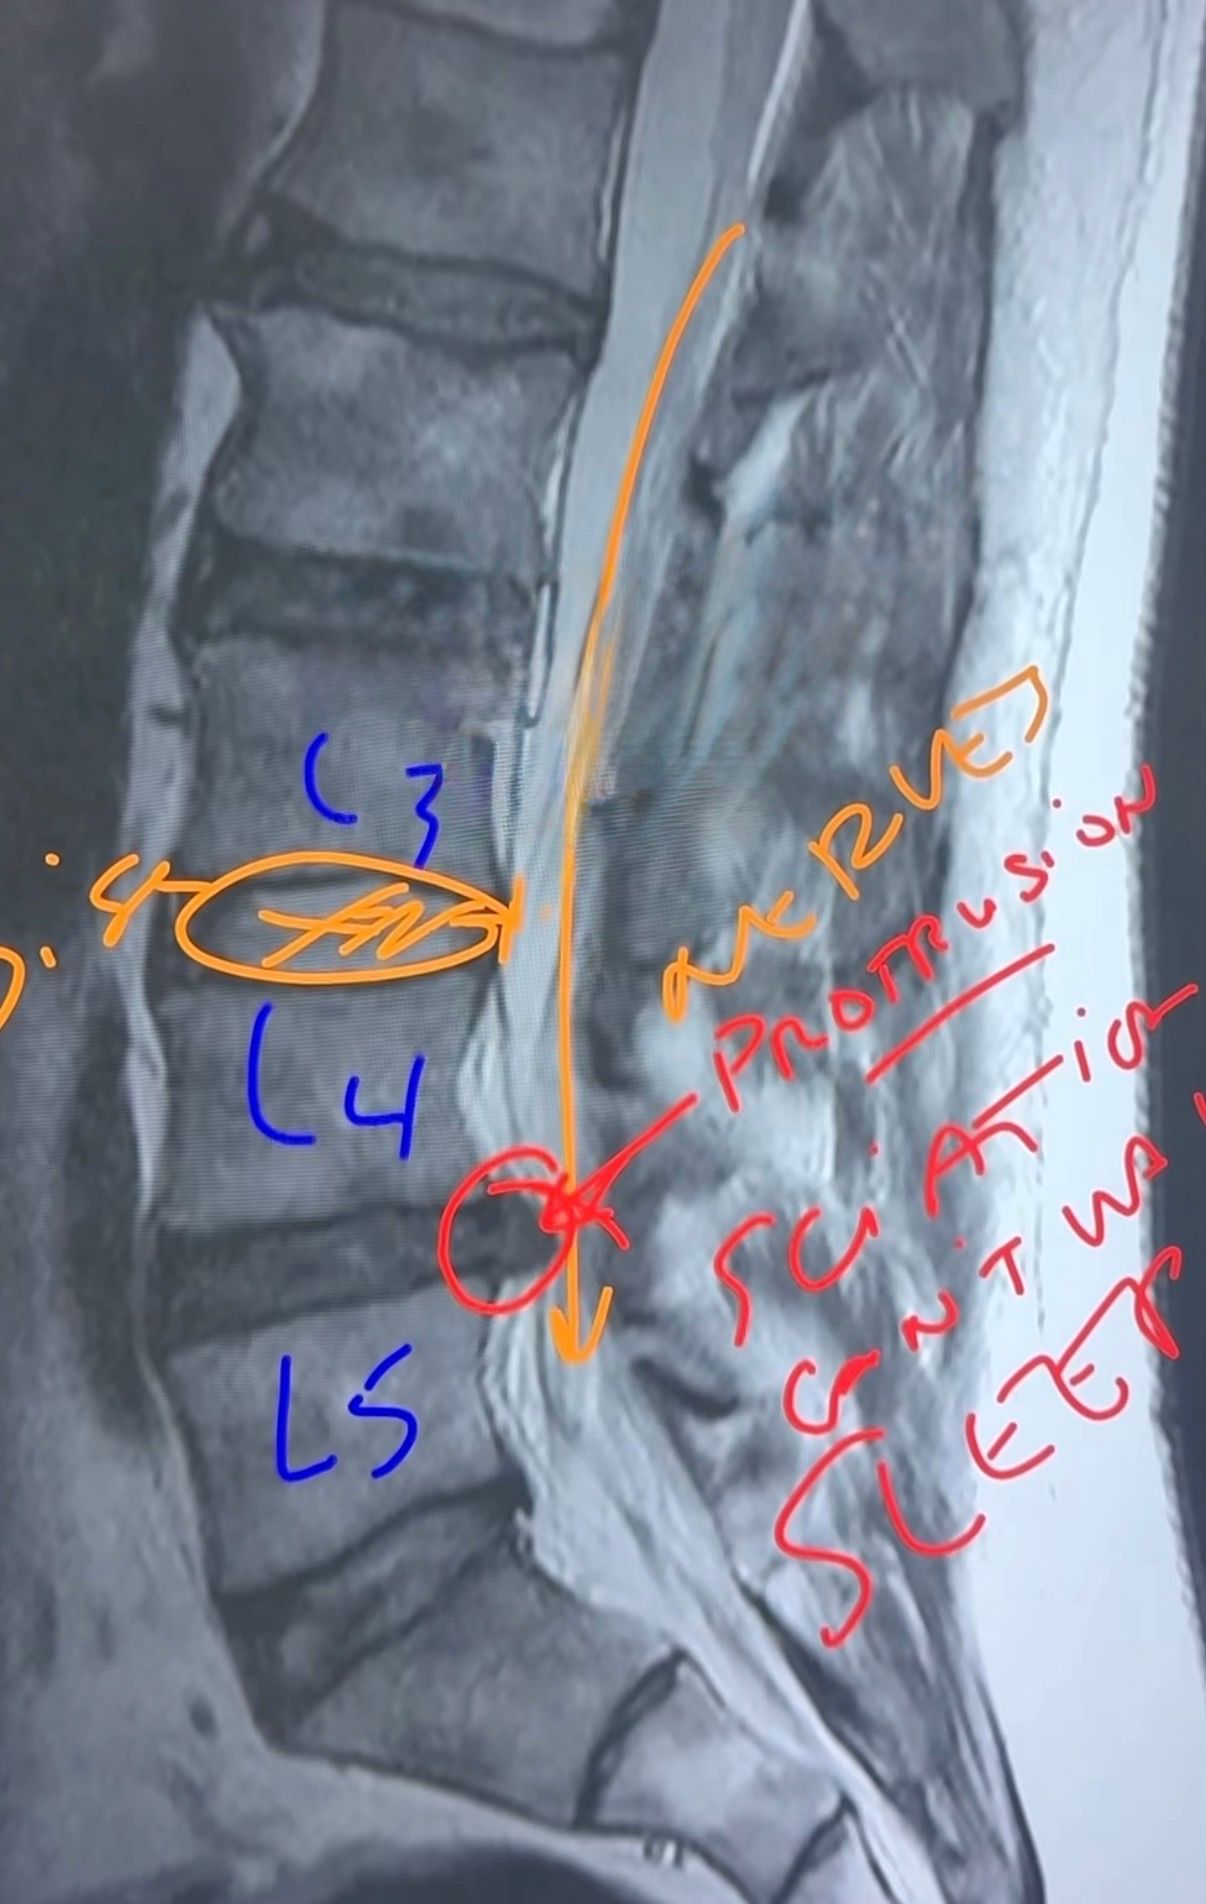

What This MRI Image Shows

In this MRI scan we are looking at the lumbar spine, specifically the vertebrae L3, L4, and L5.

The highlighted region shows a disc protrusion between L4 and L5.

Instead of sitting neatly between the vertebrae, the disc is bulging backward toward the spinal canal.

This protrusion compresses the nerve root that eventually forms part of the sciatic nerve pathway.

When the nerve is compressed, symptoms can include:

-

shooting pain down the leg

numbness

difficulty standing or walking

trouble sleeping due to pain

The MRI clearly shows how the disc is pushing into the nerve space, creating irritation.